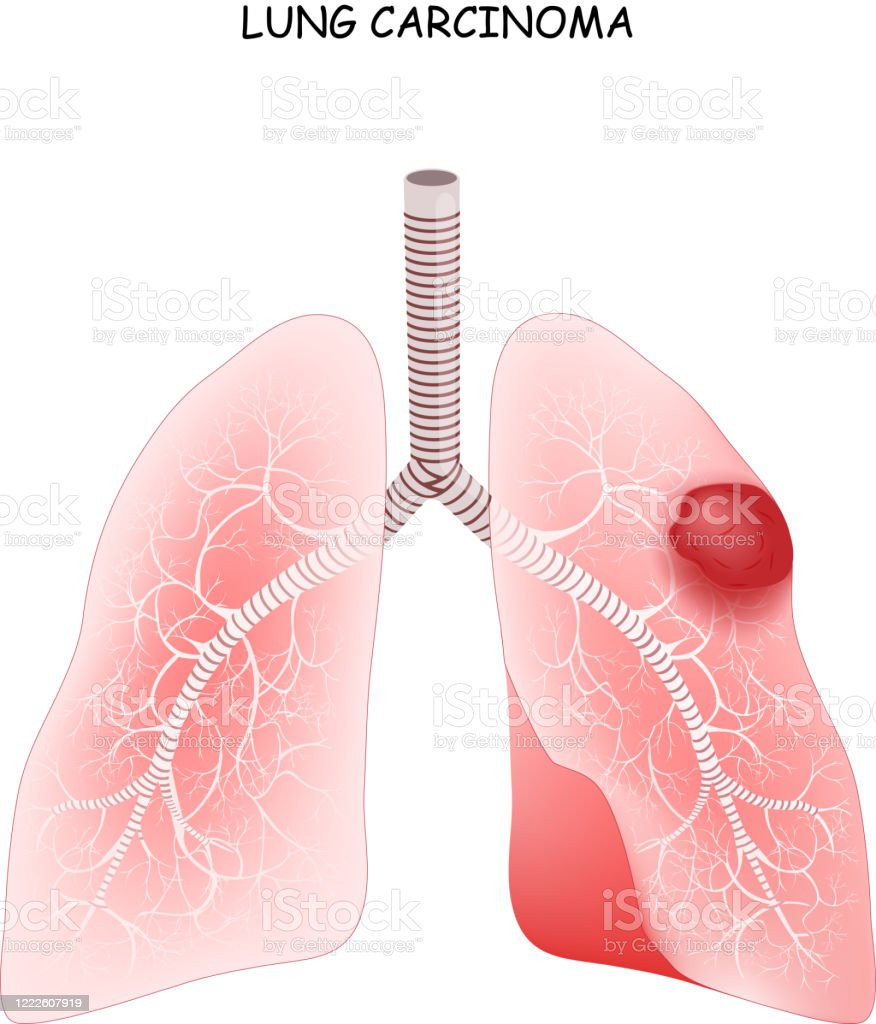

TAG: karsinoma paru

karsinoma paru

"Karsinoma Paru"